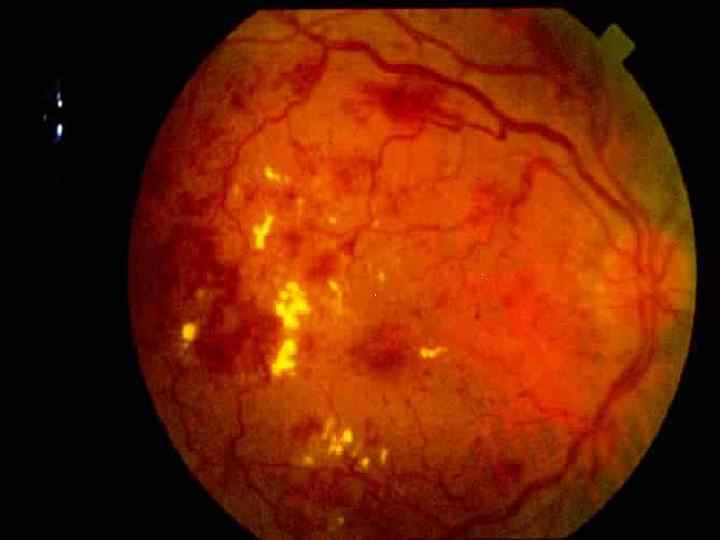

Патогенез Продолжающееся распространение этих сосудисто-пролиферативных элементов к сетчатке и, в некоторых случаях, в стекловидное тело приводит к появлению кровоизлияний Способствует фиброзу и разрастанию глиальной ткани с последующими витреоретинальными тракциями и окончательной отслойки сетчатки.

Патогенез Продолжающееся распространение этих сосудисто-пролиферативных элементов к сетчатке и, в некоторых случаях, в стекловидное тело приводит к появлению кровоизлияний Способствует фиброзу и разрастанию глиальной ткани с последующими витреоретинальными тракциями и окончательной отслойки сетчатки.

Симптомы Недоразвитость сосудов сетчатки глаза Аномальные образования из соединительной ткани в области сетчатки Затем и хрусталика

Симптомы Недоразвитость сосудов сетчатки глаза Аномальные образования из соединительной ткани в области сетчатки Затем и хрусталика